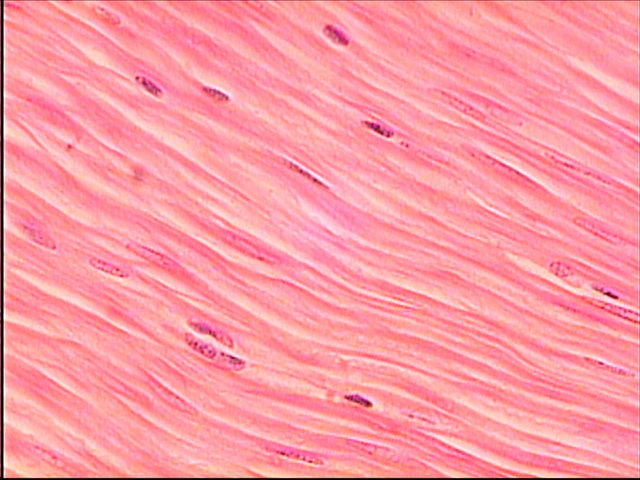

tissue

albert von Roelliker was the firs to describe tissues